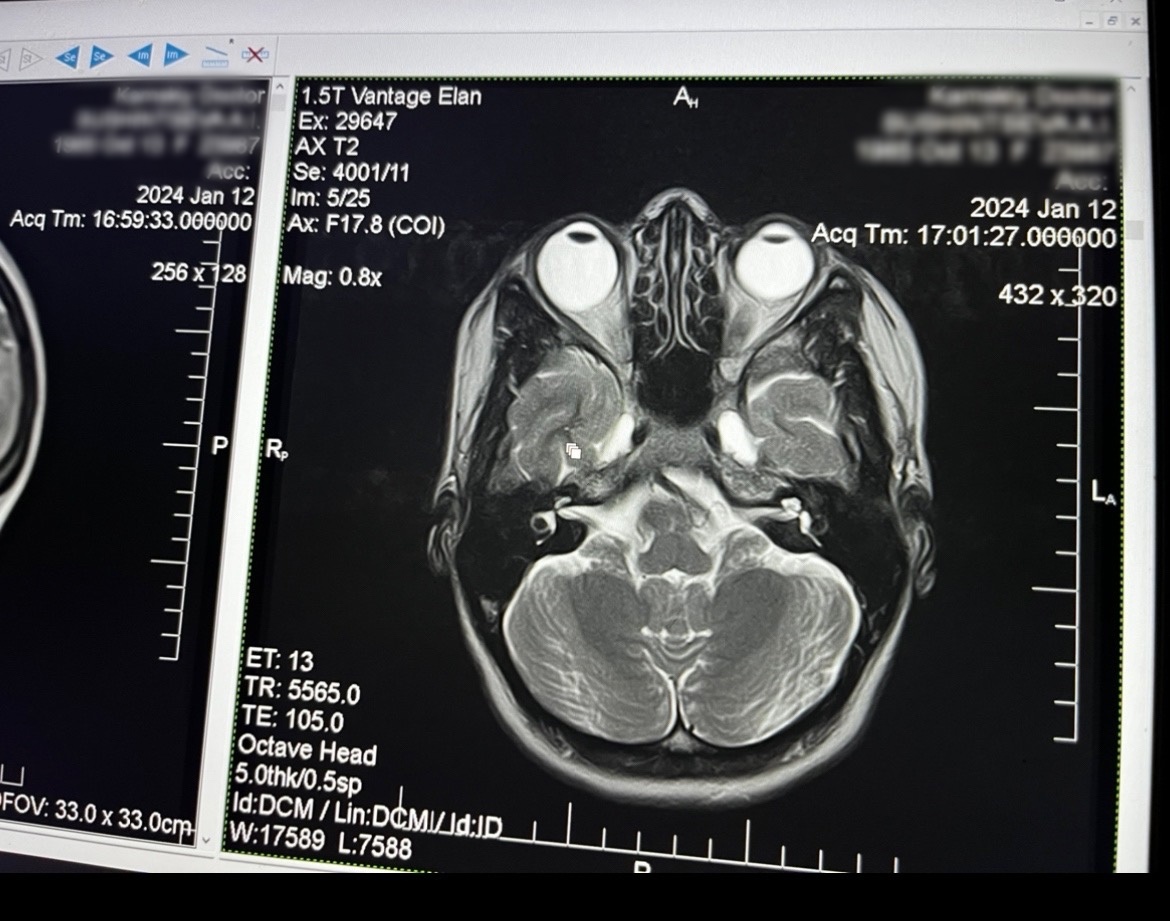

Вот, посмотрите на эту фотографию:

Здесь вы видите томографию мозга девушки, у которой на левом глазу близорукость в -12 диоптрий, а на правом -4. И вы видите как её левый глаз значительно больше правого. Он не сдавлен мышцами. Он просто тупо больше. Если бы он был сдавлен мышцами с боков, то его удлинение было бы обеспечено тем, что его поперечное сечение становилось меньше. Но оно не становится меньше.

Помните, 1 мм удлинения глаза прибавляет ему 3 диоптрии оптической силы, что делает его более приспособленным под чёткое видение вблизи без энергозатрат. Как видите, здесь левый глаз удлинён минимум на 4 мм (поэтому на нём 12 диоптрий). А правый на 1.3 мм (поэтому на нём 4 диоптрии).

И обратите внимание на хрусталик каждого глаза (тёмная чашечка в передней части глаза). Заметьте, что на левом глазу, который явно больше, хрусталик более выпуклый. Это свидетельствует о том, что он сжат цилиарной мышцей. То есть эта мышца находится в спазме. А как вы помните, спазм цилиарной мышцы (а именно мышцы Мюллера), если его долго удерживать – это именно то, что вызывает гарантированный рост глаза. Видите, как всё сходится?

К сожалению, эта девушка, не смотря на то, что и так имеет сильно удлиненный левый глаз – она настойчиво продолжает стимулировать его дальнейшее удлинение тем, что сохраняет на нём спазм аккомодации. А сохраняет его потому, что продолжает смотреть много вблизи в контактных линзах для дали. Позже мы разберём как именно линзы и очки помогают вашим глазам удлиняться, если вы их неправильно используете.